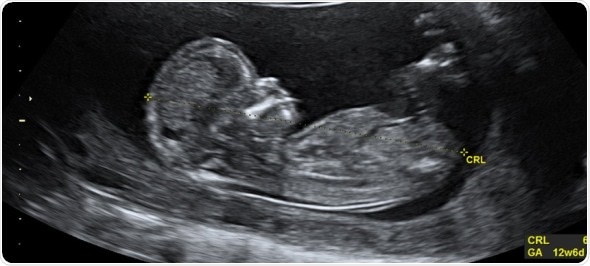

Genetic testing gives answers on developmental disorders during pregnancy. Image credit: Dr Wolfgang Moroder, Wikimedia commons